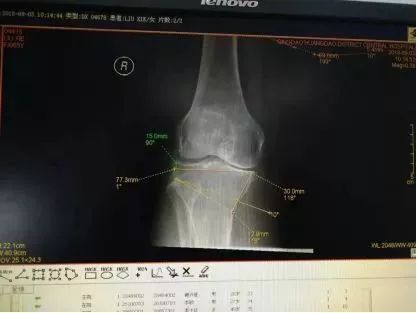

经过精准测量术前设计截骨力线,截骨角度及截骨高度

术中预行手术截骨治疗,术前检查需矫正10度,垫高14MM